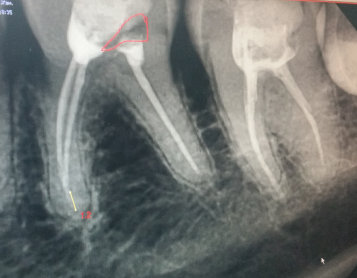

У меня треснул зуб (семерка нижняя), в нем стоит пломба, уже давно, но полтора года назад меняла т.к. старая вылетела. Тогда же и удалили нервы. Вчера ночью лопнул зуб. Отошла от пломбы часть с внутренней стороны, где язык и часть, где стык с восьмеркой. Лопнул до основания, держится на десне. Вырывать сама боюсь. Шестерки рядом уже нет, лет пять. Не хочу удалять и этот зуб.

Можно как-то его сохранить? И что делать сейчас?

Все зависит от характера скола стенки, если разрушение ниже уровня десны, то, к сожалению, зуб удаляется, хотите вы этого или нет. Причина скола кроется в неправильном решении, полтора года назад необходимо было вместо пломбы восстанавливать зуб коронкой и в этом случае ничего бы не произошло. Обратитесь к врачу, окончательный диагноз можно поставить на очном приеме.